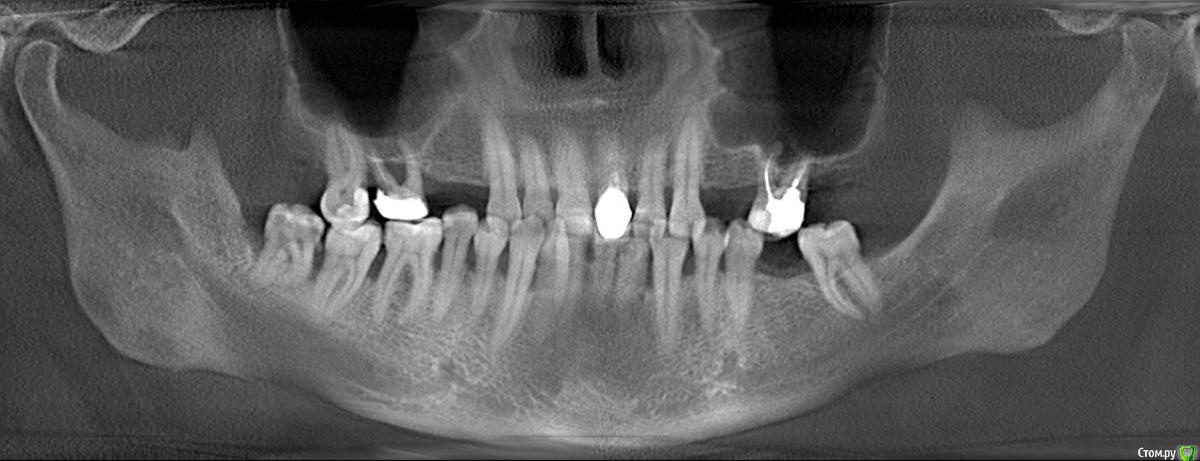

Vldmr28 Опубликовано 28 ноября, 2020 Поделиться Опубликовано 28 ноября, 2020 Доброго дня, готовлюсь к протезированию (квадротти) на верхней челюсти. Врач на осмотре приговорил к удалению два верхних зуба (шестерки). Вариантов и смысла для лечения по его мнению нет. Так как удалить, как мне кажется, успею, хотелось бы для себя понять - можно ли их вылечить и оставить. Буду признателен за любые советы. ЗД имеется. Ссылка на комментарий

сирена Опубликовано 28 ноября, 2020 Поделиться Опубликовано 28 ноября, 2020 Я согласна с врачом.Плюс 48 бы удалила(пародонтит,нет антагониста) 2 Ссылка на комментарий